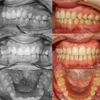

Şeffaf Plaklarla Tedavi, Lingual Ortodontik Tedavi, Şeffaf ve Metal braketlerle Sabit Ortodontik Tedavi, Hareketli / Fonksiyonel Çene Ortopedisi, Ortognatik Cerrahi ve Obstrüktif Uyku Apnesi tedavi uygulamaları yapmaktayım.

Sınıf 3 Malokluzyonlar

Diş Çapraşıklığı

Sınıf 2 Malokluzyonlar

Sınıf 1 Malokluzyonlar